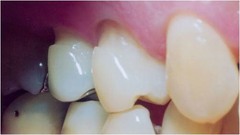

pericornitis

-Erythematous, painful, swollen tissue around the crown of a partially erupted tooth